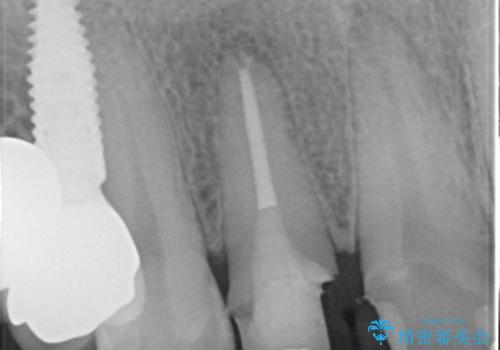

虫歯のマイクロスコープによる丁寧な除去、根管治療、深い虫歯に対する挺出(エクストリュージョン)および歯周外科を行ったのち精度の高いセラミッククラウン製作治療を計画します。

虫歯の放置により、根管治療や深い虫歯に対する処置が必要になりましたが丁寧に一つづつ処置を行ったことで抜歯をすることなく歯を残すことができました。